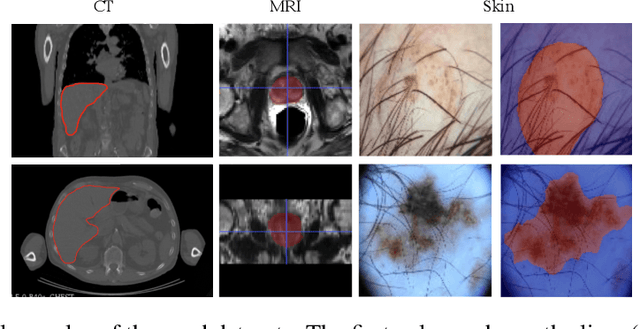

Abstract:Skip connections in deep networks have improved both segmentation and classification performance by facilitating the training of deeper network architectures, and reducing the risks for vanishing gradients. They equip encoder-decoder-like networks with richer feature representations, but at the cost of higher memory usage, computation, and possibly resulting in transferring non-discriminative feature maps. In this paper, we focus on improving skip connections used in segmentation networks (e.g., U-Net, V-Net, and The One Hundred Layers Tiramisu (DensNet) architectures). We propose light, learnable skip connections which learn to first select the most discriminative channels and then attend to the most discriminative regions of the selected feature maps. The output of the proposed skip connections is a unique feature map which not only reduces the memory usage and network parameters to a high extent, but also improves segmentation accuracy. We evaluate the proposed method on three different 2D and volumetric datasets and demonstrate that the proposed light, learnable skip connections can outperform the traditional heavy skip connections in terms of segmentation accuracy, memory usage, and number of network parameters.